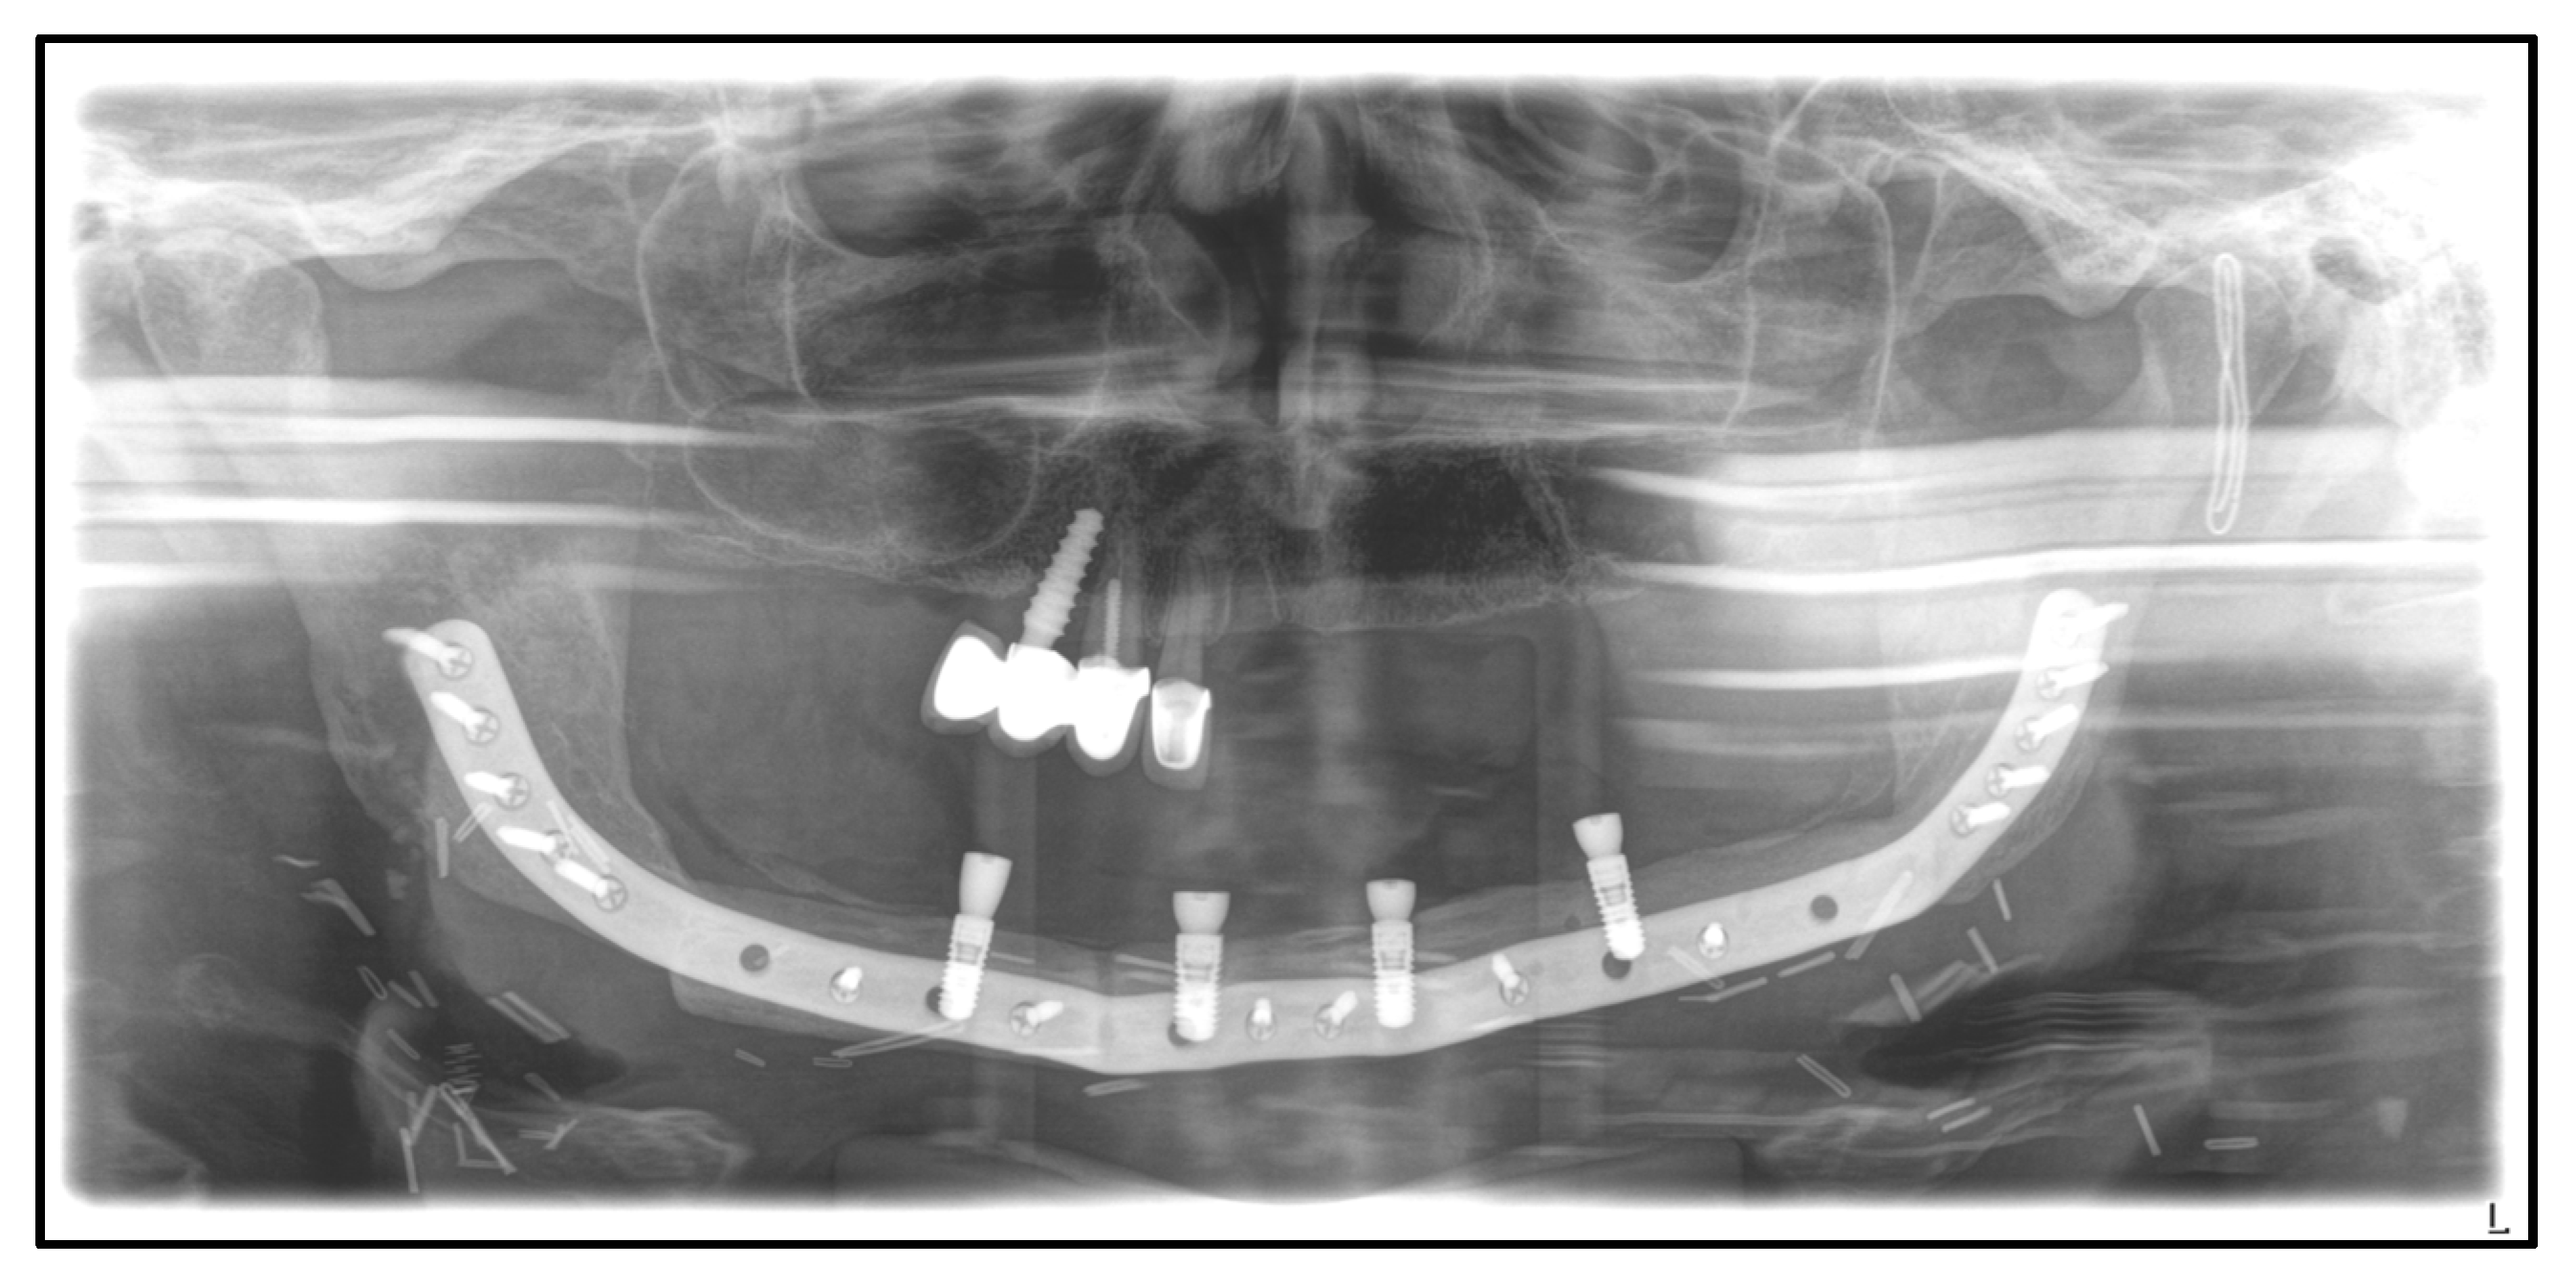

| April 2020: | Partial mandibular resection from the left to the right mandibular angle, CAD/CAM-assisted reconstruction using a free fibular graft and PSI, temporary tracheostomy. In the course: development of aspiration pneumonia treated with piperacillin and tazobactam 4.5 g for 8 days. |

| April 2021: | Placement of four dental implants in the neo-mandible for dental rehabilitation. |